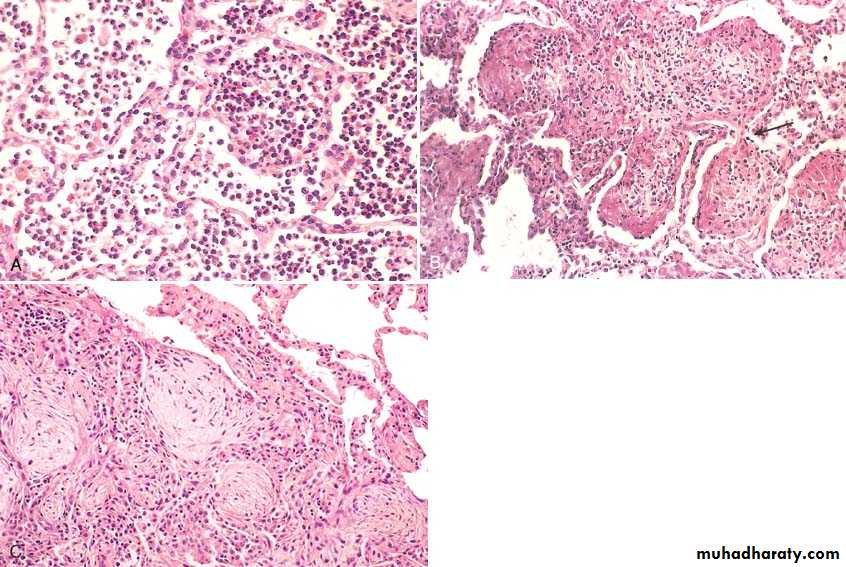

histologic spectrum of pneumonia may vary from .fibrinopurulent (acute bacterial)

mononuclear interstitial infiltrate ( viral )

granulomas and cavitation ( chronic pneumonias)

In the era before antibiotics, pneumococcal pneumonia involved entire or almost entire lobes and evolved through four stages: congestion, red hepatization, gray hepatization, and resolution. Early antibiotic therapy alters or halts this typical progression, so if the person dies, the anatomic changes seen at autopsy may not conform to the classic stages.

During the first stage, that of congestion, the affected lobe(s) is (are) heavy, red; histologically, vascular congestion can be seen, with proteinaceous fluid, scattered neutrophils, and many bacteria in the alveoli. Within a few days,

the stage of red hepatization ensues, in which the lung lobe has a liver-like consistency; the alveolar spaces are packed with neutrophils, red cells, and fibrin

In the, gray hepatization, the lung is dry, gray, and firm, because the red cells are lysed, while the fibrinosuppurative exudate persists within the alveoli

Resolution follows in uncomplicated cases, as exudates within the alveoli are enzymatically digested to produce granular, semifluid debris that is resorbed, ingested by macrophages, coughed up, or organized by fibroblasts

The term "primary atypical pneumonia" was initially applied to an acute febrile respiratory disease characterized by patchy inflammatory changes in the lungs, largely confined to the alveolar septa and pulmonary interstitium.The term "atypical" denotes the moderate amounts of sputum, absence of physical findings of consolidation, only moderate elevation of white cell count, and lack of alveolar exudates.

Chronic pneumonia is most often a localized lesion in an immunocompetent person, with or without regional lymph node involvement. There is typically granulomatous inflammation, which may be due to bacteria (e.g., M. tuberculosis) or fungi.